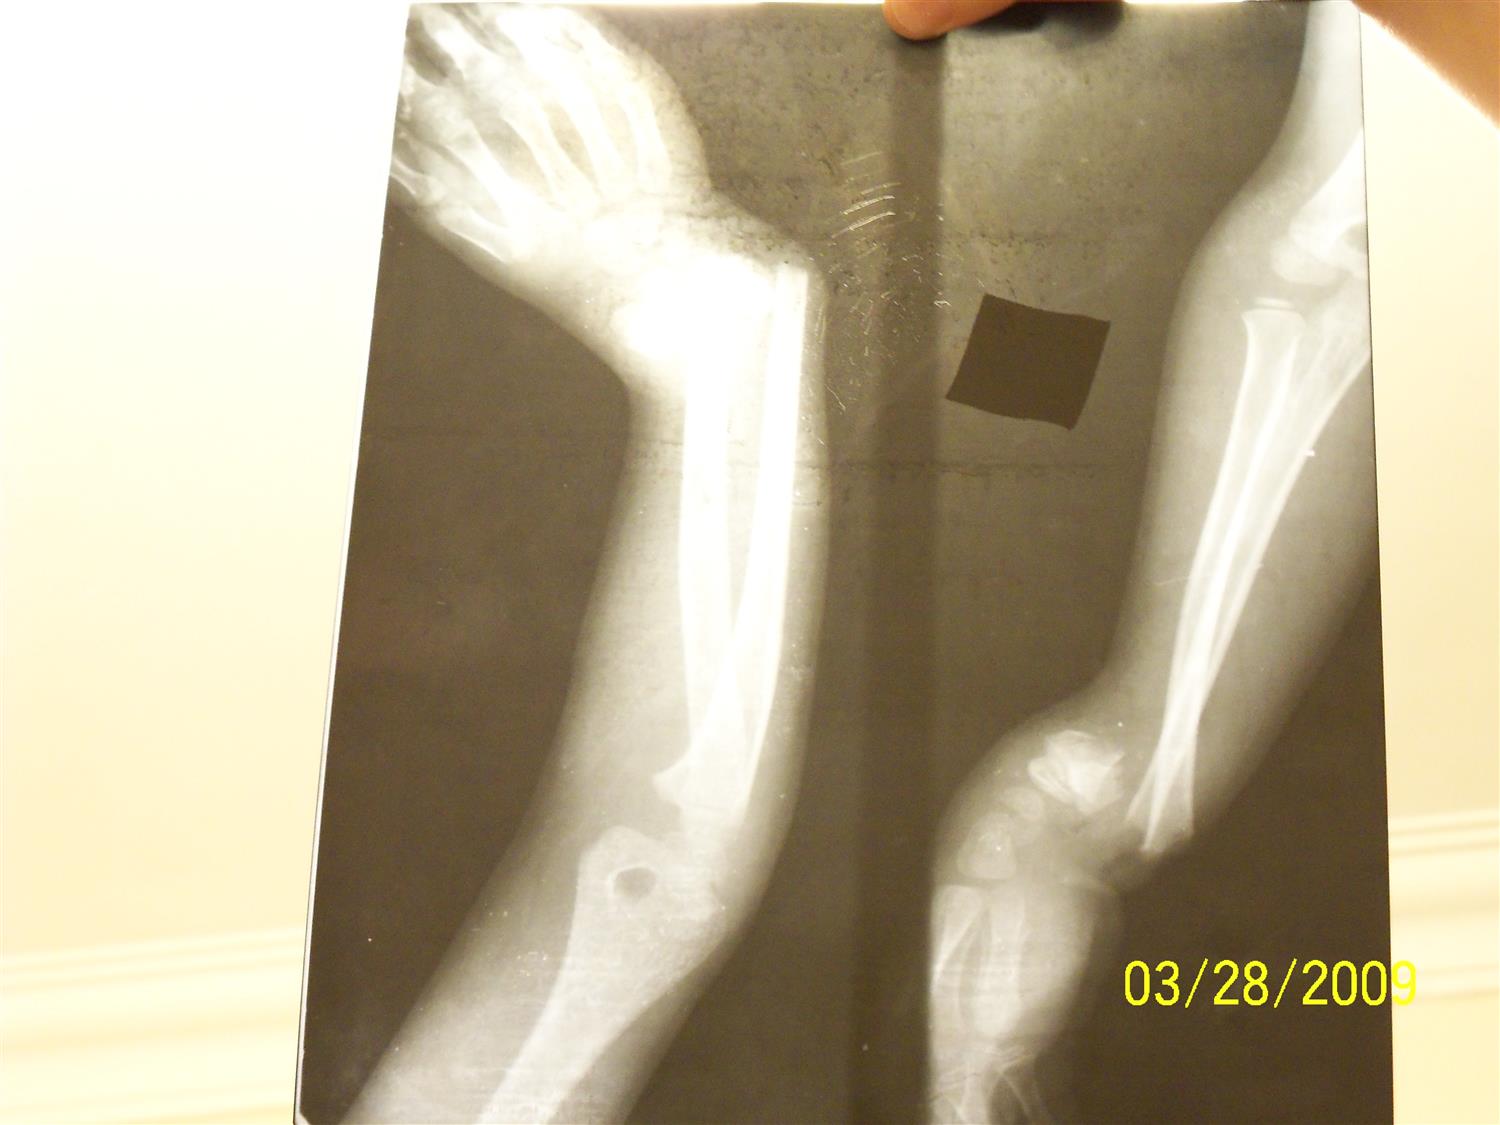

Midshaft radius and ulna fractures Distal Radius Ulna Fracture Pediatric The initial management of distal forearm fractures in children will be reviewed here. Physical exam for forearm injuries. Fractures involving the distal radius and ulna are commonly seen in children and adolescents. Distal radius fractures are the most common orthopaedic injury and generally result from fall on an outstretched hand. Evaluate simple and complex forearm fractures. Diagnosis is made clinically. Distal Radius Ulna Fracture Pediatric.

13yearold boy with left distal radiusulna fracture treated with Distal Radius Ulna Fracture Pediatric Distal radius fractures with associated druj disruption, commonly termed galeazzi fractures, are most often the result of axial loading of the wrist with extreme pronation. Physical exam for forearm injuries. Acceptable alignment for distal radius fractures in adolescent patients is based on three major determinants: Distal radius fractures are the most common orthopaedic injury and generally result from fall on. Distal Radius Ulna Fracture Pediatric.